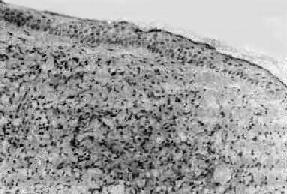

图18-18 瘤型麻风

表皮萎缩变薄,真皮内有泡沫细胞的弥漫浸润,后者与表皮层间有一薄层无细胞浸润区相隔